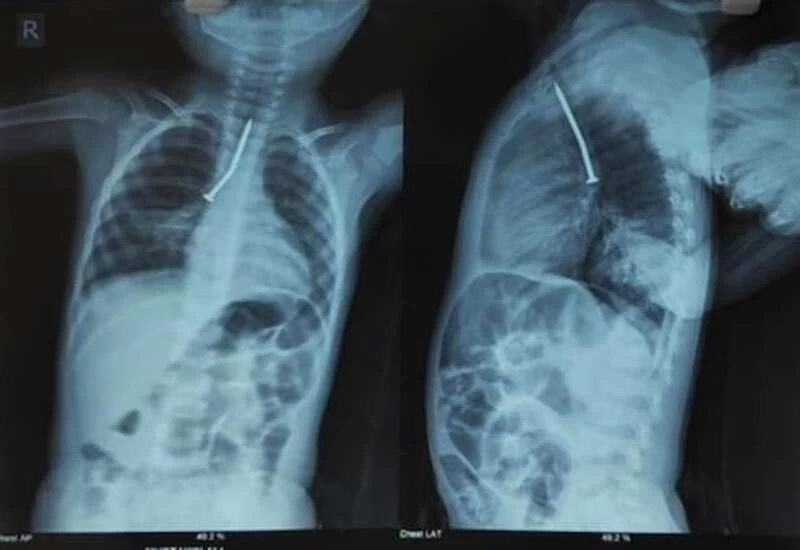

According to SSKM management, Mustakin's surgery started at 7 pm on Sunday. Dr. Under the leadership of Arunav Sengupta, 4 doctors' team had made their operations. According to him, the nail was stuck in the child's respiratory tube. It was reversed and there was a problem in breathing.